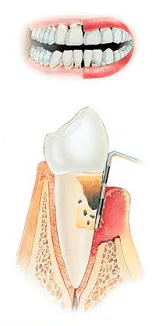

Стадии пародонтита

3 стадия |

4 стадия |

До недавнего времени в Омске использовали только очень болезненный способ лечения пародонтита с помощью уколов, теперь в нашей клинике применяется инновационный безболезненный подход к лечению десен с мощью лазера. Прочитать подробнее о лечении пародонтита с помощью лазера.

Стоимость лечения пародонтита около 5 000 ₽, конечная стоимость зависит от степени поражения. Пародонтит также как и чистку зубов необходимо делать регулярно (раз в пол года, максимум 1 раз в год), при этом лечение пародонтита стоит в 2 раза дороже!